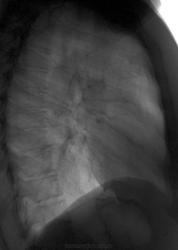

Сегодняшние флюшки. Женщина жалуется на простуду (кашель, субфибрилитет), бронхиты часты, пневмоний никогда не было. Думаю, без онко тут не обойдется, хотя в лоб пока не высказал. Намекал на КТ - нет денег. Сошлись на пневмонии с дальнейшим контролем. Какие будут мнения?

Опухоль в тройке. Если не КТ, то хотя бы линейку.

Возможно и в 3-ке, но больше склоняюсь к средостению

Увеличение лимфоузлов средостения, слева тоже непорядок.

Более склоняюсь к опухоли в S3.Конечно,нужна томография(любая).Спасибо,Игорь Иванович,за демонстрации случаев,а то из-за праздников на сайте затишье.

В 13 году справа были интересные изменения, может еще и туберкулез выплывет

Склоняюсь за пер.рак. Дообследование